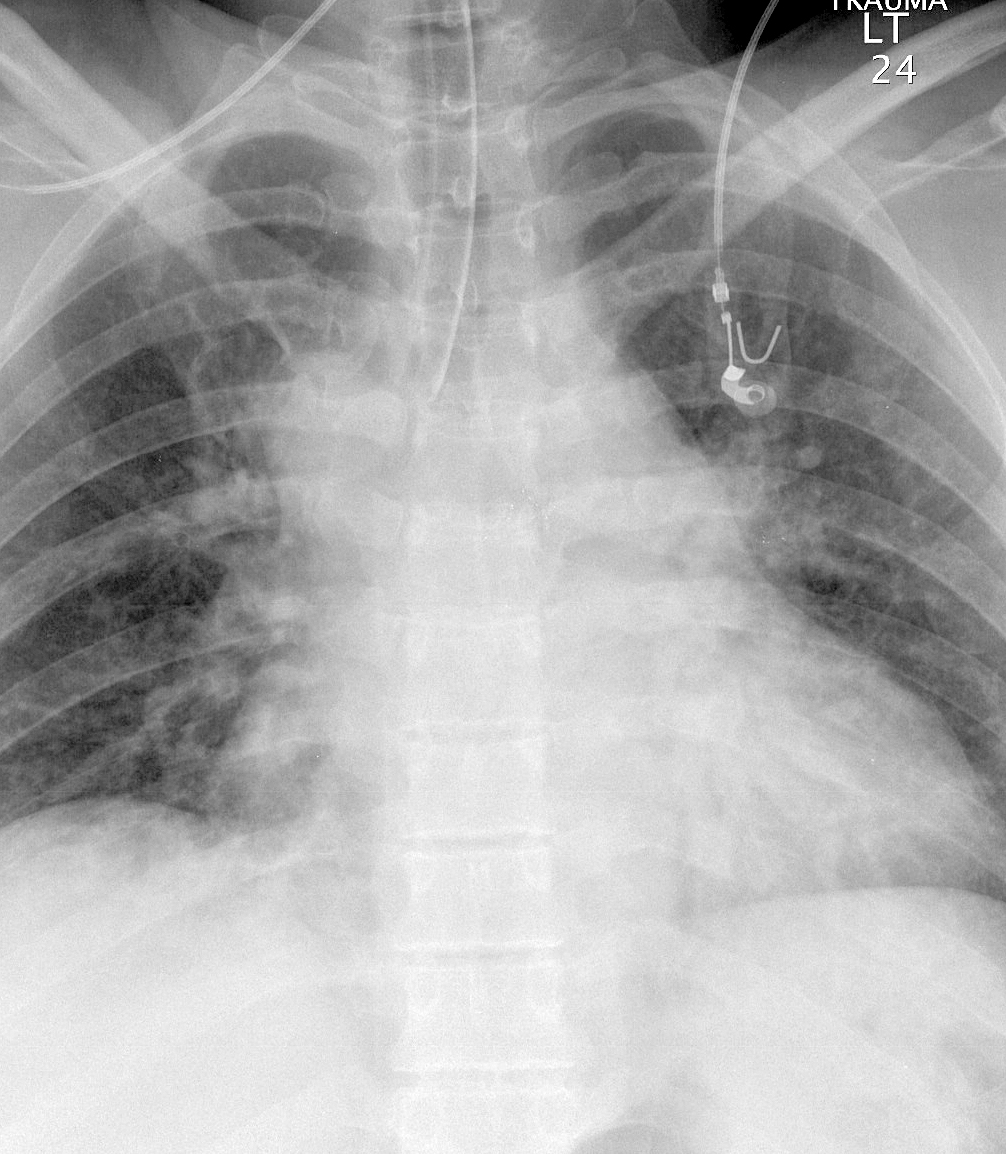

Azygous Continuation 2a